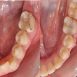

Interdisciplinary Treatment of Patients with Deep Overbite and Parafunctional Activity

Bruxism is defined as parafunctional grinding of teeth and due to the excessive wear of the posterior teeth, patients with long-standing bruxism often have pathological deep overbite. For many decades, treatment of bruxism and deep overbite was focused on reshaping the bite for achieving an occlusion free of deviations. Despite large efforts, the management of bruxism and subsequent deepening overbite was not obtained.